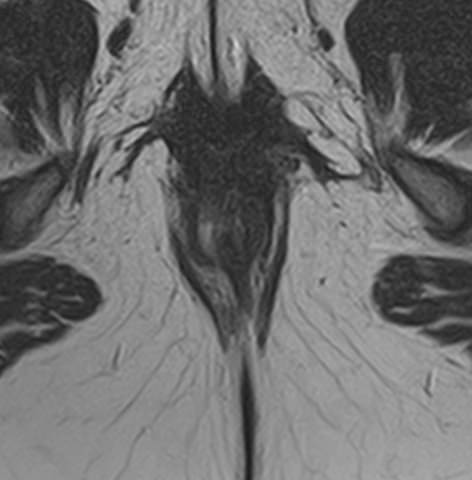

МРТ аноректальной области с контрастным усилением – это специализированное исследование, используемое для детального изучения структур и патологий в области ануса, прямой кишки и окружающих тканей. Контрастное усиление помогает улучшить видимость кровеносных сосудов и определить границы патологических образований.

• Опухоли и новообразования: Оценка размера, распространения и характера опухолей прямой кишки и аноректальной области.

• Воспалительные заболевания: Диагностика и оценка распространенности воспалений, таких как проктит, флегмона, абсцессы.

Преимущества МРТ аноректальной области включают высокую детализацию мягких тканей и отсутствие ионизирующего излучения. Контрастное усиление помогает лучше визуализировать сосуды и патологические изменения.

В целом, МРТ с контрастным усилением является безопасной и информативной процедурой для диагностики различных заболеваний аноректальной области.